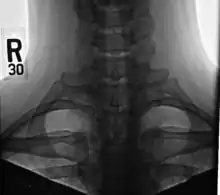

Côte cervicale

Une côte cervicale chez l'homme est une côte supplémentaire qui provient de la septième vertèbre cervicale. Leur présence est une anomalie congénitale située au-dessus de la première côte normale. On estime qu'une côte cervicale survient chez 0,2 %[1] à 0,5 %[2] (1 sur 200 à 500) de la population. Les personnes peuvent avoir une côte cervicale à droite, à gauche ou des deux côtés[3].

À l'imagerie, les côtes cervicales peuvent être distinguées car leurs apophyses transverses sont dirigées inférolatéralement, alors que celles du rachis thoracique adjacent sont dirigées antérolatéralement[7].